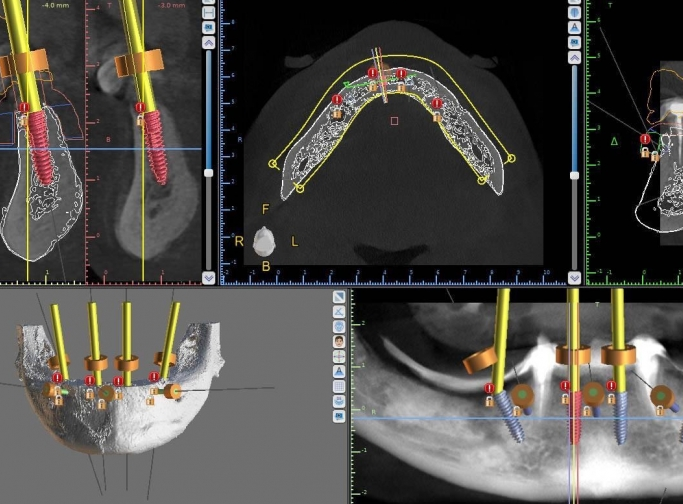

Vă prezentăm un caz All-on-4 finalizat cu succes cu ajutorul a 2 ghiduri chirurgicale realizate 100% cu ajutorul tehnologiei digitale.

Am folosit doua ghiduri: unul pentru osteoplastia crestei alveolare, iar cel de-al doilea pentru inserarea implanturilor.